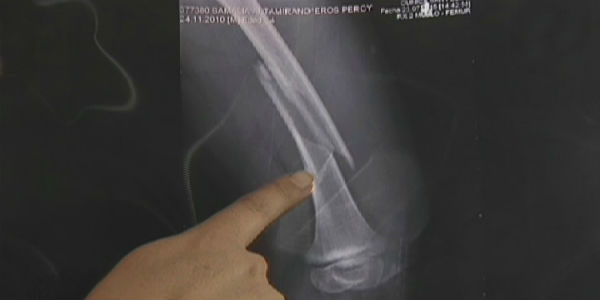

Los padres del pequeño Eros aún esperan la respuesta del colegio Divino Maestro de Chorrillos. El menor sufrió un grave accidente cuando jugaba en un carrusel y hasta ahora la institución no se ha pronunciado al respecto. Sin embargo, la directora Rocío Vilcahuaman Loyola se reuniría en los próximos días con los padres del niño, que prácticamente ha sido abandonado a su suerte.